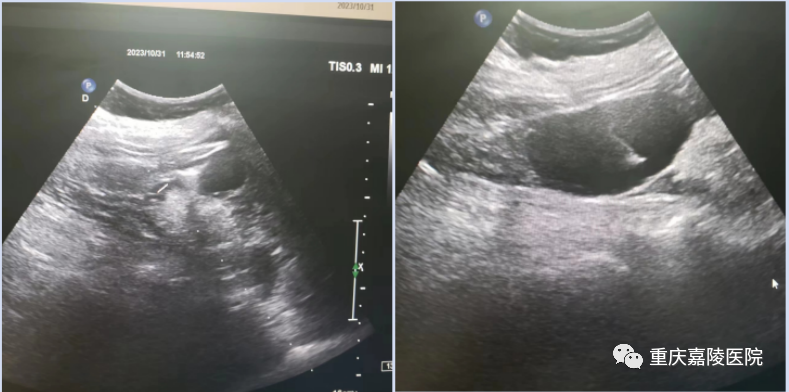

近日,我院超声科成功对一老年女性“左肾囊肿”进行抽液硬化治疗,效果良好。

该患者因“左侧腰部疼痛”入院,彩超显示:左肾中下极实质性一囊肿,直径约7厘米。经过全面的术前评估后,决定对左肾囊肿行超声引导下抽液硬化治疗,以解除其对腰部的压迫症状。穿刺引流术中,通过控制抽液速度,尽量减轻压力变化给患者带来的不适,共计抽液105ml,患者血压、心率平稳,无不良反应,再通过注入硬化剂,治疗完成。